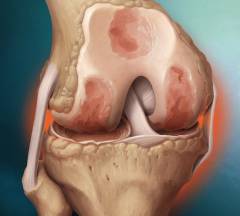

Особенности строения коленного сустава

Коленный сустав образован тремя костями:

- Мыщелки бедренной кости.

- Мыщелки большеберцовой кости.

- Надколенник.

Особые элементы коленного сустава:

- Суставные мениски – справа и слева. Мыщелки бедра имеют большие размеры по сравнению с мыщелками большеберцовой кости. Это несоответствие устраняется за счет хрящей, которые находятся в полости сустава – наружного и внутреннего коленных менисков. Верхняя поверхность мениска идеально сочетается по форме и размерам с мыщелком бедренной кости, а нижняя – с мыщелком большеберцовой кости. Кроме того, мениски работают как амортизаторы. Нередко артроскопию проводят при подозрении на их повреждение.

Внутрисуставные крестообразные связки. Они крест-накрест соединяют бедро с большеберцовой костью, укрепляя сустав. Подозрение на повреждение крестообразных связок также нередко становится показанием к артроскопии. -

Синовиальные сумки (небольшие мешочки из соединительной ткани, заполненные синовиальной жидкостью). Вокруг коленного сустава их находится около 10 штук. Некоторые из них сообщаются с суставной полостью.